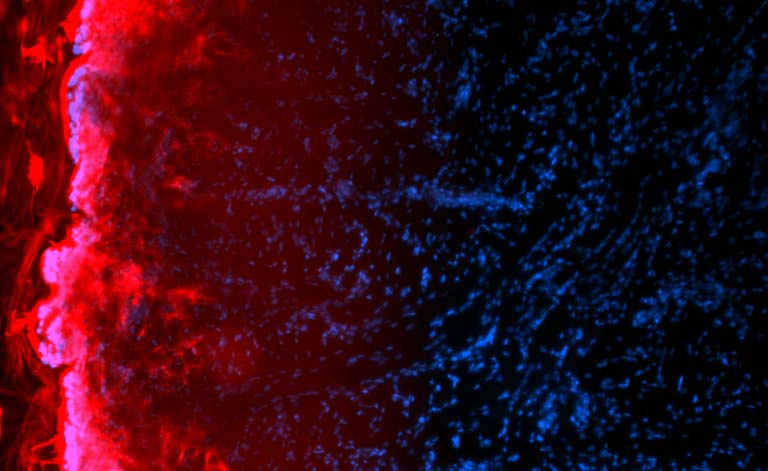

This image is the surface of a freshly harvested pig’s tongue. The blue indicates the cells, the red indicates the nanoparticles that permeate into the tongue. We were examining the permeation of our chemotherapeutic nanoparticle in to the tongue for topical treatment of oral cancer. With oral HPV cancer on the rise, we are determined to develop a local anticancer treatment with very limited toxicity. This treatment can be much more effective than the current treatment and has the potential to significantly reduce the systemic side effects of chemotherapy.